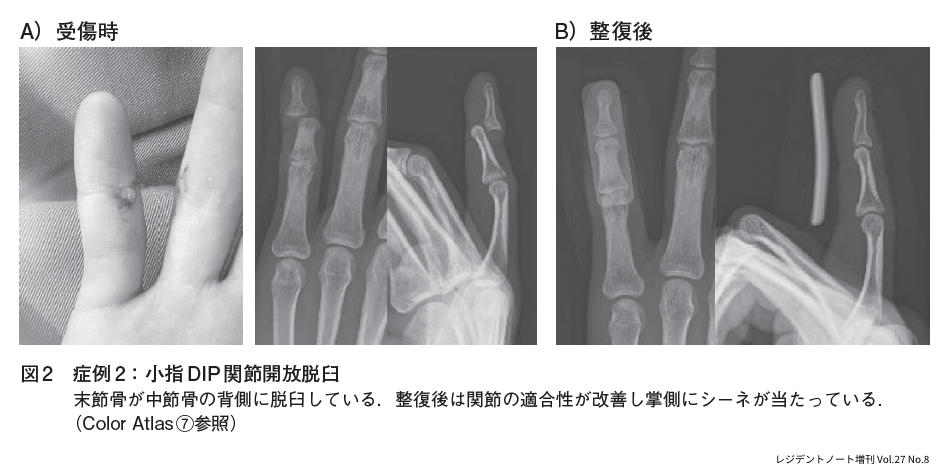

症例2:指脱臼

30歳代男性.野球プレー中に打者が打ったボールが直接小指に当たり受傷した(図2).小指DIP関節橈側に開放創があり骨の露出があった.X線検査では小指DIP関節の背側脱臼があり,DIP関節開放脱臼と診断した.局所麻酔後に洗浄し徒手整復を行い創部を閉創,アルフェンスシーネ固定を行った.